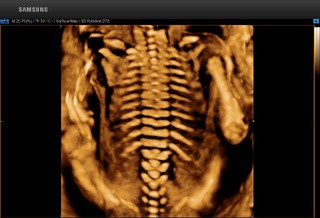

超高细微分辨率的图像质量以及超高灵敏度的低速血流检测能力,能够全方位的分析并提高病变检出率,通过全球领先的智能分析和诊断技术,显著提高了诊断准确率,孕期病变检出率提高到98%,并大大降低了误诊和漏诊率。

检查的项目有:面部排畸、羊水检查、消化系统、神经系统、泌尿系统、骨骼系统、循环系统、胸部疾病(心脏检查)。

↓↓正常脊柱 ↓↓半椎体畸形